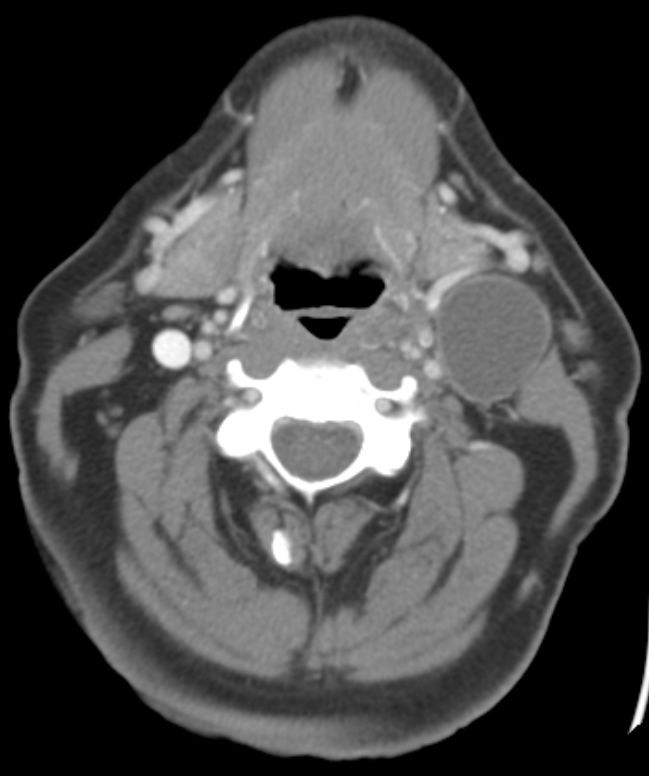

66-jähriger Mann mit einem zystischen 34mm großen Knoten links am Hals.

Die Panendoskopie ergab ein 11mm großes invasives Plattenepithelkarzinom der linken Tonsille. pT1 pN2a(1/15) Mo G3 p16+. | |||